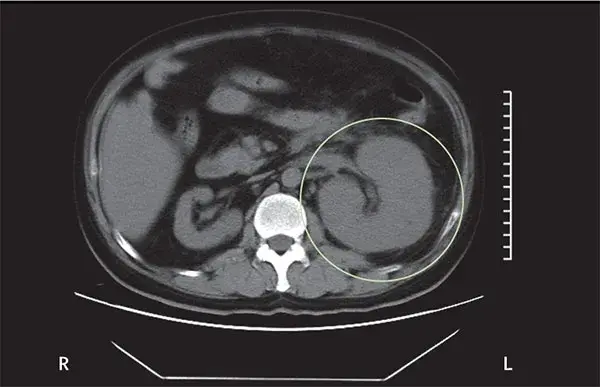

Uma causa incomum de hematúria glomerular intermitente!

Uma causa incomum de hematúria glomerular intermitente!

Hematúria pós infecção, caso clínicos para auxiliar no entendimento de causas glomerulares comuns e raras...